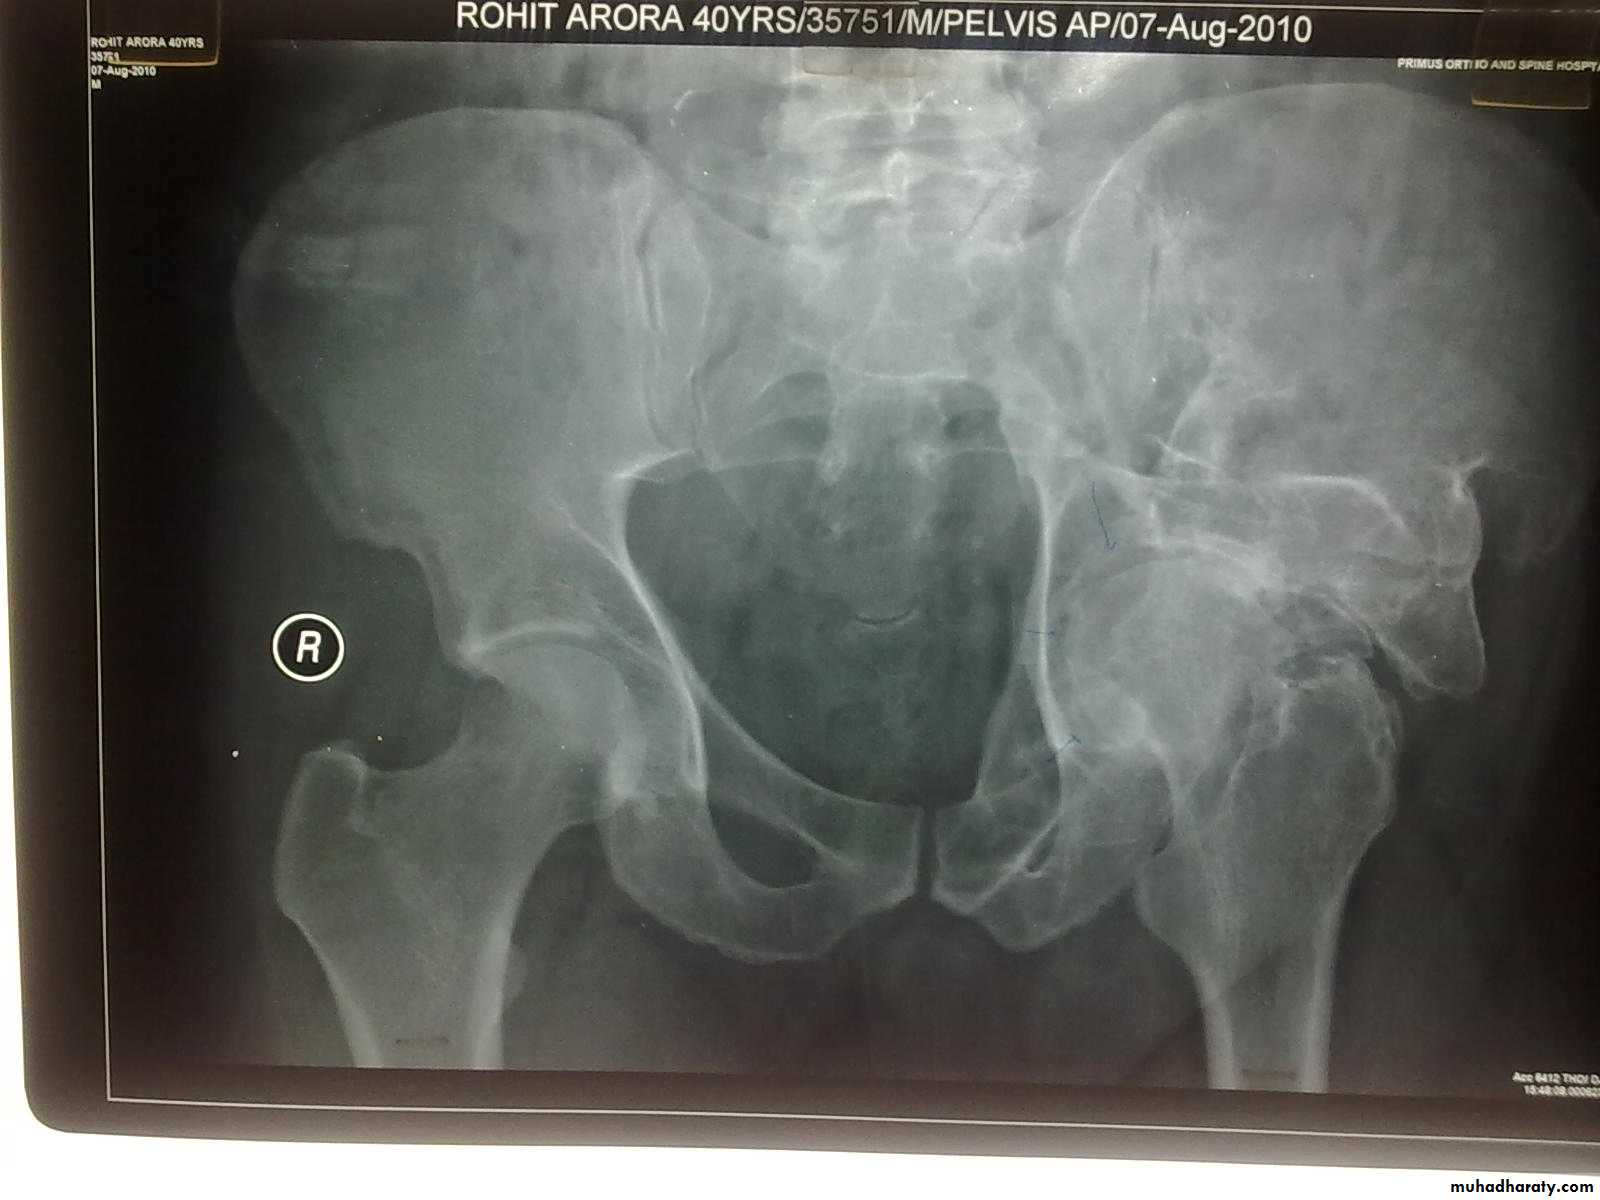

Traumatic anterior hip dislocation:Mechanism :

Road traffic accident ,miner, building laborer who is leg wide .

knees straight .

Back bent forward.

Clinically:

O\ELeg external rotation.

Abducted and slightly flexed.

Bulging head seen laterally and also feel.

Hip movement impossible.

Neurovascular examination necessary.

Radiological examination:

Hip dislocated either superior, inferior in relation to the acetabulum.Treatment: